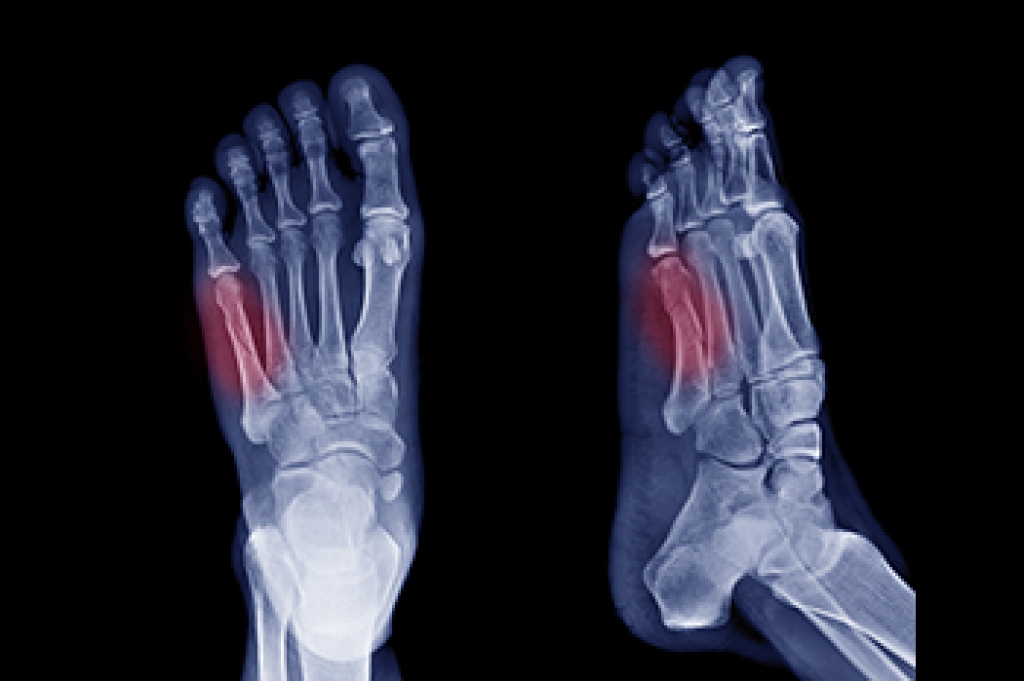

A plantar fibroma will not disappear without treatment, but it can get smaller and be a non-issue. If pain persists, a podiatrist examines the foot and when the arch of the foot is pressed, pain can be felt down to the toes. An MRI or biopsy might be performed to help diagnose or evaluate the plantar fibroma. The following non-surgical options are generally enough to reduce the size and pain of these nodules:

Surgery is considered if the mass increases in size and the patient continues to feel pain after non-surgical methods are tried.